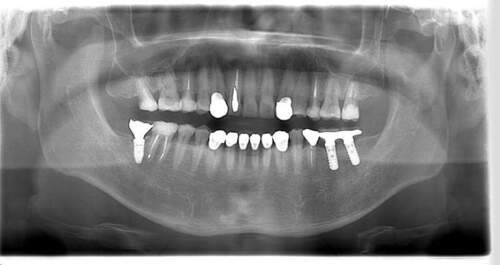

インプラント治療の症例2

レントゲン写真

- Befor

- After

口腔内写真

| 年齢 | 50代・男性 |

|---|---|

| 主訴 | 左上7番 左下5番7番 |

| 治療内容 | ・インプラント埋入 ※1:GBR(骨造成)・・・骨再生誘導法。骨の高さや厚みを人工骨や人工膜などを使用し再生する方法 |

| 治療費 | 合計:1,809,500円(税込) ■内訳 ・左上7番 ・左下5番7番 |

| 治療期間 | 左上7番約1年 左下5番7番約10ヵ月 |

| 治療方針 | 左上7番は昔他院で被せものをしており、被せものの中が歯ぐきの中まで虫歯になっていたため抜歯せざるを得ない状態だった。抜歯と同時に骨造成を行い、骨が出来るまで4ヵ月待ってからインプラントを埋入した。 ※2ポンティック・・・歯のない部分を補うダミーの歯。 |

| 担当者所見 | 元々金属の被せものが多く入っていたため、2次カリエス※3が多かった。今回は金属ではなく、ジルコニアを使用し、2次カリエスにならないよう、患者様にはブラッシング指導とメンテナンスの重要性をお伝えした。 ※3二次カリエス・・・詰め物や被せものを入れた歯が虫歯になること。 |